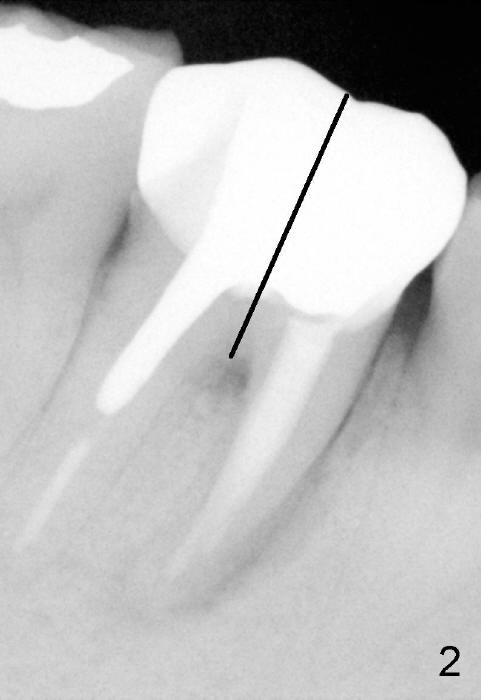

Try to remove the crown with forceps and section the tooth (Fig.2 black line) for easy tooth removal (Fig.3: using proximators).